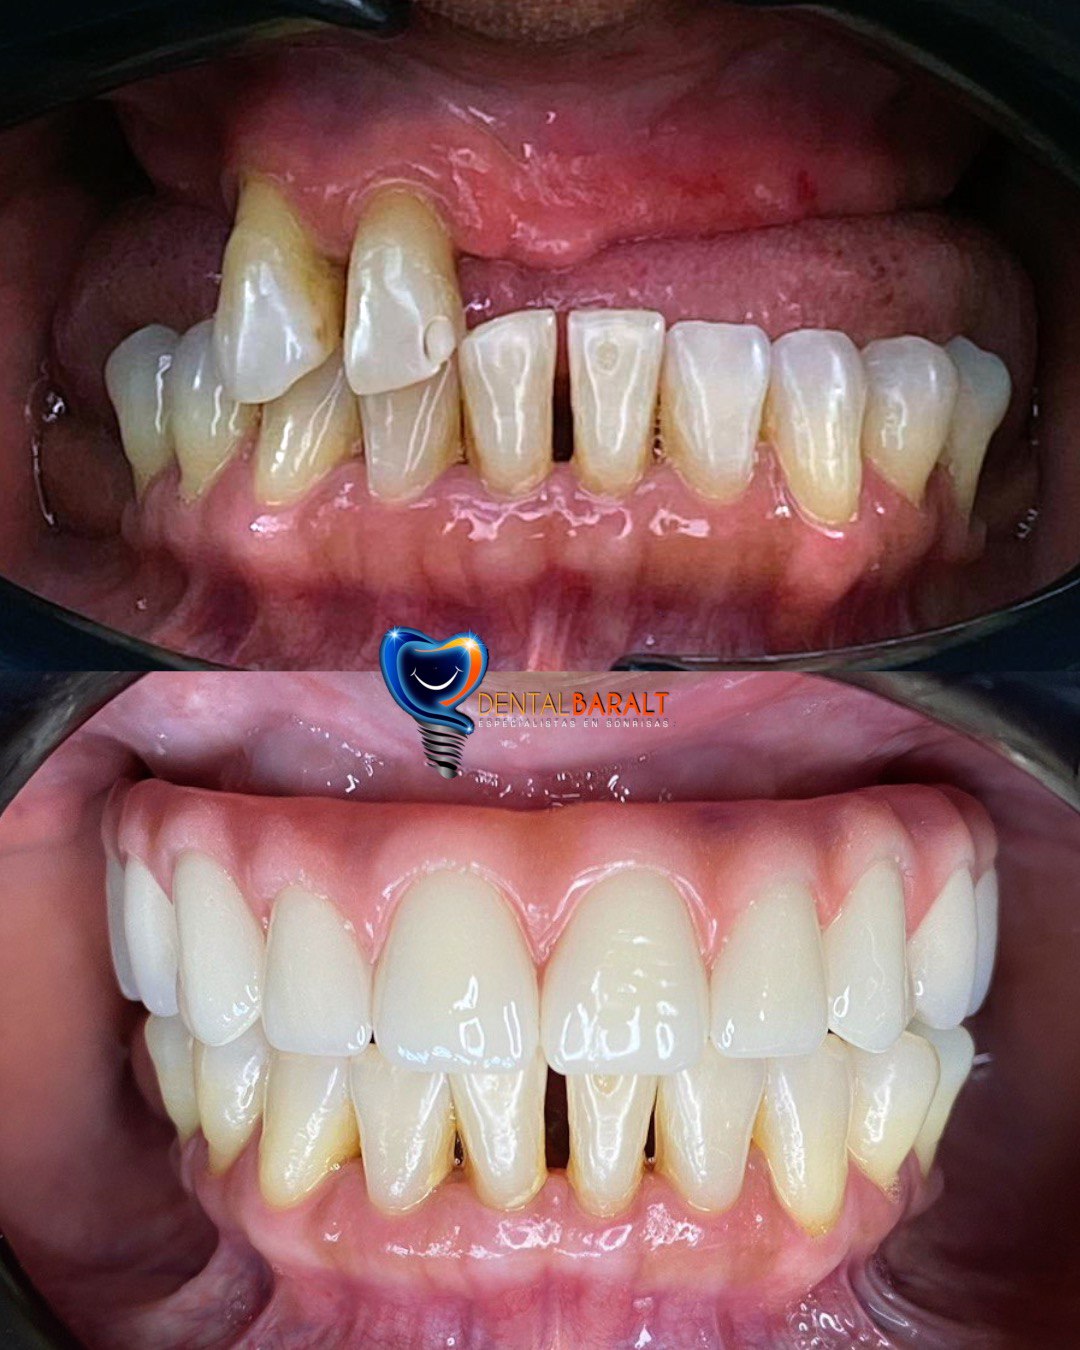

Desde prótesis parciales hasta prótesis completas, tenemos la solución ideal para recuperar tanto la funcionalidad como la estética de tu boca.

Nuestras prótesis están diseñadas para ser cómodas, de fácil uso y para durar mucho tiempo, devolviéndote tu capacidad para masticar, hablar y sonreír con confianza.

Usamos materiales resistentes y estéticos para garantizar que tu prótesis se vea y funcione como dientes naturales.

Mejoran la función masticatoria y la estética dental y facial, permitiéndote comer y sonreír con confianza mejorando considerablemente la autoestima del paciente.

Cuando estés en presencia de ausencias dentarias, y estas pueden ser reemplazadas de distintas maneras entre ellas tenemos el grupo de las fijas y el grupo de las removibles, así como también realizamos prótesis de mayor envergadura como coronas sobre implante y prótesis hibrida.